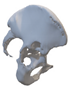

The most appropriate stem length and position could then be determined without penetrating the cortical bone of the linea terminalis []. The goal was to have at least 2–3 mm of bone all around the stem of the cup (Figure 2a).

Figure 2.

Design steps of the aiming device: (a) Stemmed acetabular cup with guiding wire; (b) drawing of the guiding sleeve and the reference points; (c) connection of the reference points and the guiding sleeve; and (d) adjustment of the handle.